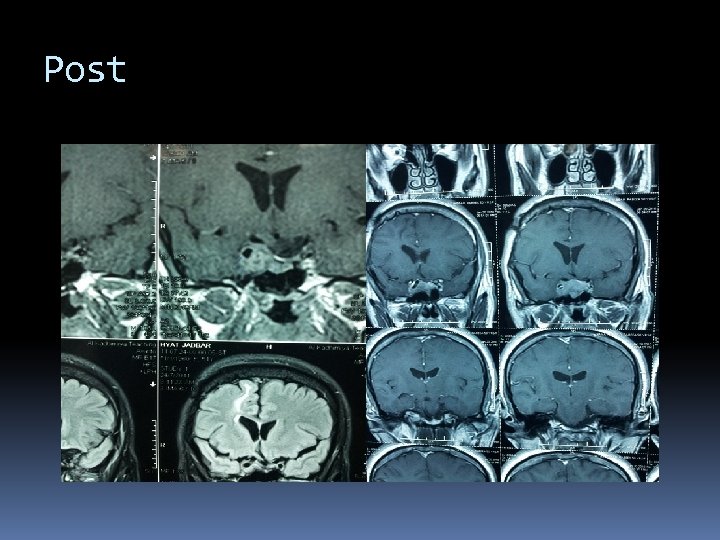

Pre.

Post

Post medical.